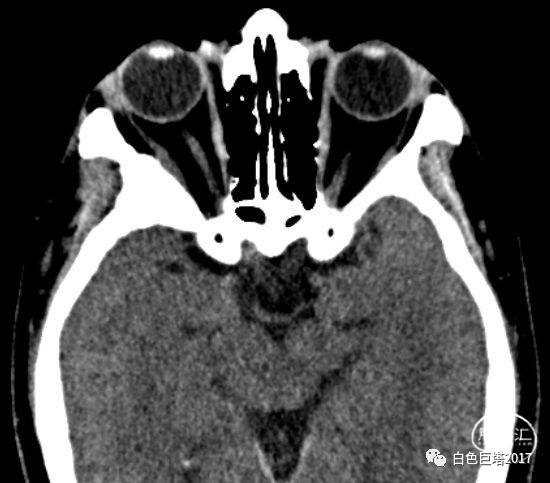

入院头颅CT检查提示右侧颞骨-眼眶后外侧壁骨质改变,眶内未见明显占位。报告考虑骨纤维异常增殖症可能性大。

3Dslicer重建可见眶后外侧壁骨质不均匀增厚,毛糙。

入院讨论病情,患者以突眼为主要症状,无眼球活动障碍,无炎性症状,无眶内占位,无甲状腺功能异常。结合患者入院头颅眼眶CT重建检查及既往MRI表现,考虑蝶骨嵴脑膜瘤可能,同时不能除外颅骨纤维异常增殖症。